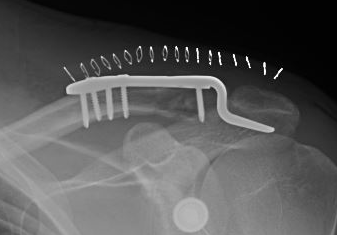

Dorsal locking plate +/- CC ligament reconstruction

Hook plate

Dorsal locking plate +/- CCL reconstruction

Disadvantage

Lateral screws under significant tension and subsequently higher rate of screw/plate pull-out

Sufficient lateral bone to obtain fixation

Consider having hook plate available / supplement with coraco-clavicular fixation

Dorsal locking plate with cerclage fibretape